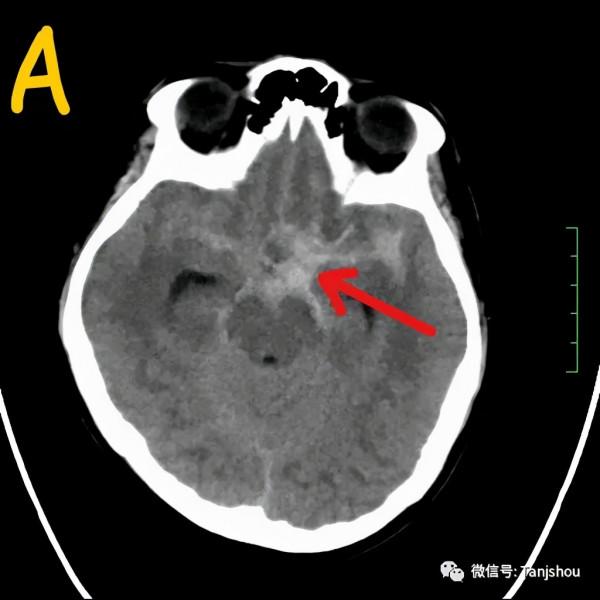

放射科醫生:顱腦CT平掃影象可見鞍上池、側裂池及腦溝高密度影填充,提示大量蛛網膜下腔出血,考慮動脈瘤破裂,需要等待CTA重建影象出來才能確診。(影象A和B的紅色箭號)